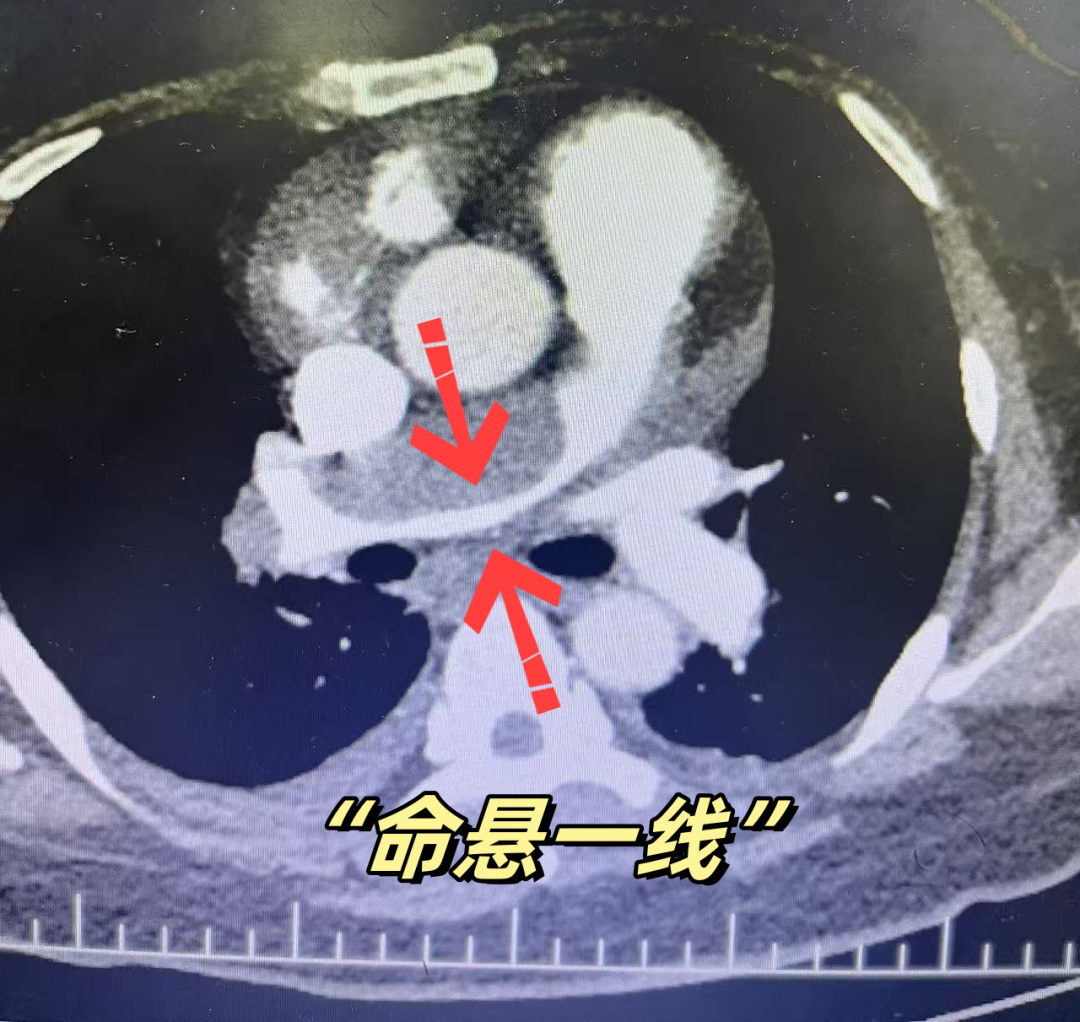

险象环生:重症肺栓塞致命悬一线

徐矿总医院接诊后,第一时间启动急诊绿色通道,迅速完善肺动脉成像及肺动脉造影等相关检查,同步组织胸心外科、麻醉科、介入科、重症医学科等多学科专家会诊。检查结果显示,张女士右主肺动脉几近完全闭塞,左主肺动脉部分栓塞,肺部供血严重受阻,血氧饱和度持续下降。巨大的血栓如同一枚“不定时炸弹”,随时可能阻断肺循环,导致患者猝死。